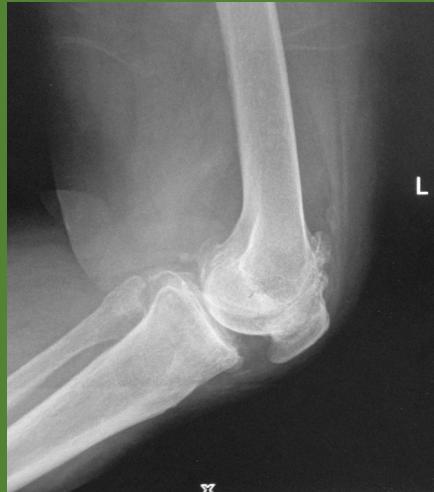

Imaging Studies

- Standard Radiographs:

- Both knees AP standing views (weight-bearing)

- Lateral views of both knees

- Skyline view (patellofemoral assessment)